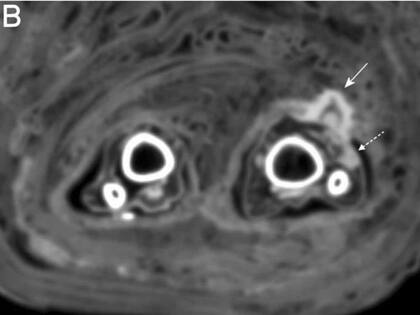

El equipo del Instituto de Estudios de Momias en Bolzona halló los vendajes mientras realizaba tomografías computarizadas de rutina de las momias

Según surge de los escaneos de esos estudios, la herida parecía haberse infectado cuando ella murió, dado que al parecer se detectaron signos de “pus”, dijo Zink. Esos signos de infección fueron marcados con flechas punteadas en los escaneos a continuación.